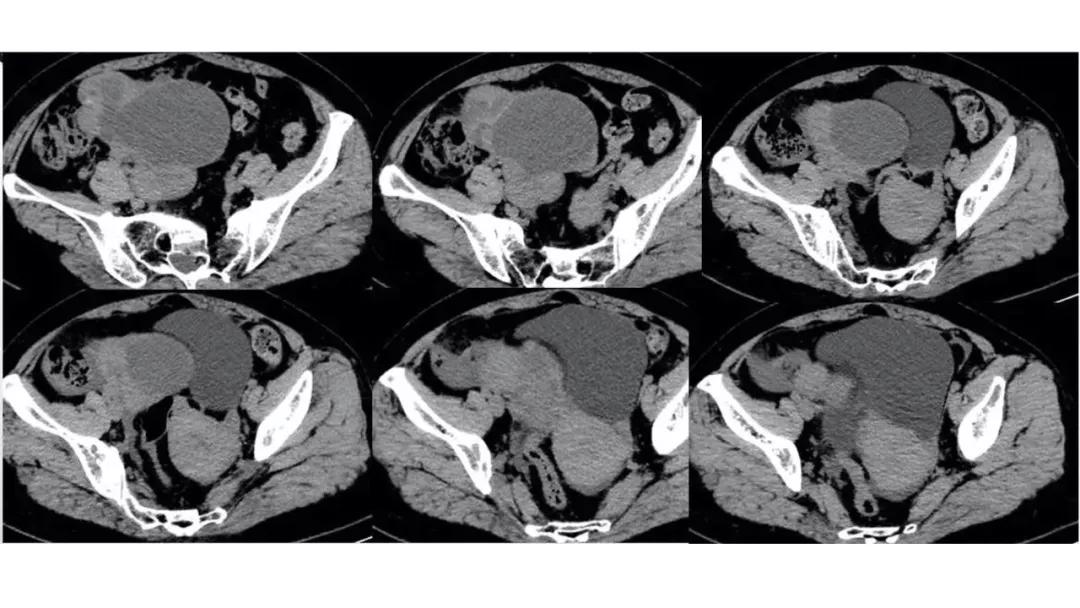

病理:浆液性囊腺癌

病理:颗粒细胞瘤